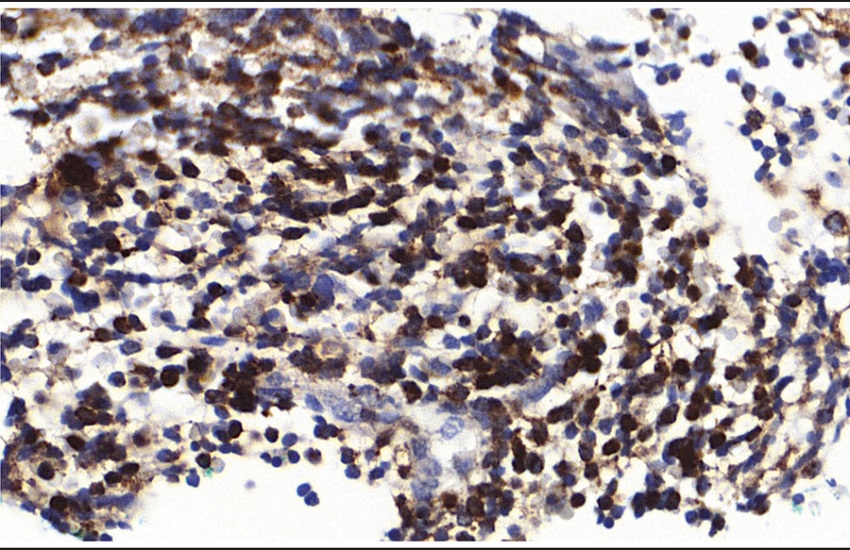

The iliac crest bone marrow biopsy exhibited marked hypercellularity due to an interstitial infiltration by malignant neoplasm with small round cells (Figure 2). There were foci of fibrosis and increased bone marrow reticulin (Figure 3). Immunohistochemical study shows positivity for CD45 (2B11 + PD7/26, Dako, ready for use), CD20 (clone L26, dilution 1:250, Cell Marque), CD79a (JCB117, Dako, ready for use, Figure 4), TdT (polyclonal, Dako, ready for use, Figure 5) and CD10 (56C6, Dako, ready for use, Figure 6), negativity for CD99 (12E7, Dako, ready for use), desmin (D33, Dako, ready for use), CD3 (polyclonal, Cell Marque, dilution 1:150), CD163 (MRQ-26, Cell Marque, ready for use) and CD1a (010, Dako, ready for use). Immunohistochemistry demonstrates positivity for CD45 (Figure 4), CD79a (Figure 5), CD20, TdT and CD10. Morphological and immunohistochemical findings were consistent with the diagnosis of acute lymphoblastic leukemia, immunophenotype B (B-ALL), with a bone primary multifocal presentation, clinically characterized by hypercalcemia, multifocal osteolytic lesions and single cytopenia. The patient received the chemotherapic protocol called BFM-2002 (Berlin-Frankfurt Munster European Group for ALL treatment) but had several clinical complications secondary to treatment and ultimately died after ten months of treatment.

Malignant neoplasm characterized by small round cell pattern.

HE hematoxilin and eosin.